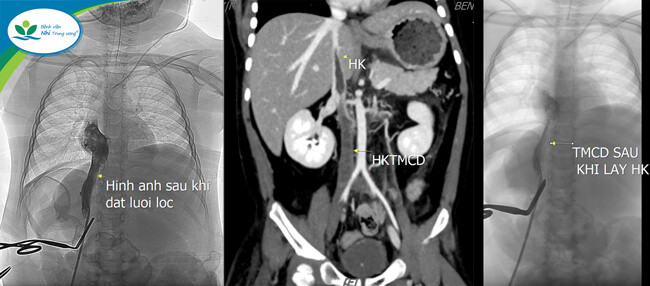

| Hình ảnh huyết khối của trẻ trước và sau khi được phẫu thuật |

“Bằng kinh nghiệm lâm sàng và xem xét tiền sử huyết khối của trẻ, chúng tôi nghi ngờ trẻ có huyết khối tĩnh mạch lớn làm cản trở dòng máu đổ về tim. Ngay lập tức, trẻ được làm các xét nghiệm cận lâm sàng, chẩn đoán hình ảnh, kết quả xác định trẻ có huyết khối lớn, liên tục từ tĩnh mạch đùi, chậu 2 bên lan đến tĩnh mạch chủ dưới và tĩnh mạch thận, nguy cơ gây tắc mạch máu phổi và mạch máu não, đe dọa tính mạng nếu không được xử trí kịp thời.” – ThS.BS Trần Hoàng – Khoa Thận và Lọc máu chia sẻ.

“Ngay từ khi hội chẩn, mục tiêu của chúng tôi là tiếp cận tĩnh mạch chủ dưới đoạn sau gan và trên thận, khơi thông dòng chảy tĩnh mạch chủ dưới, sau đó, đặt lưới lọc để tránh huyết khối trôi về tim gây thuyên tắc phổi. Rất may mắn, cuộc phẫu thuật diễn ra thành công.

Đánh giá siêu âm sau 8 giờ, trẻ tái thông dòng chảy tĩnh mạch thận 2 bên, tái thông tĩnh mạch chủ dưới đoạn sau gan và ngang tĩnh mạch thận, không có bằng chứng huyết khối trôi về tĩnh mạch phổi 2 bên” – ThS.BSCKII Lê Đình Công – Trưởng Đơn vị Điện quang can thiệp, Phó Trưởng khoa Chẩn đoán hình ảnh vui mừng chia sẻ.